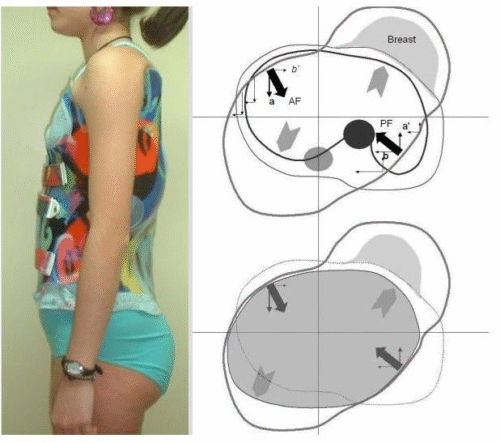

كيف يعمل حزام اعوجاج العمود الفقري؟

الحزام يعمل بطريقة ذكية تعتمد على:

- توجيه نمو العمود الفقري

- تقليل الضغط على المناطق المنحنية

- دعم الوضعية الصحيحة للجسم